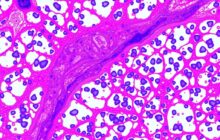

Когда речь заходит о здоровье предстательной железы, многие теряются в медицинских терминах. В этой статье ...